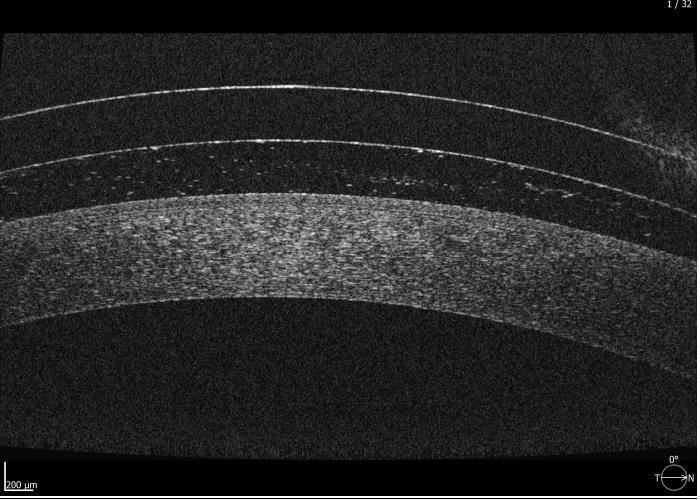

Initial maps were taken and used to design the lenses (Fig 1-3). At the patient’s aftercare appointment she was asked to wear the lenses for at least three hours (images of the lens on the eye and OCT scans are shown in Figs 4 to 7). OCT scanning is very useful in assessing post-wear fits as it allows for effective measurement of lens clearance at the apex and at the limbus, and for accurate assessment of the edge profile and its interaction with the sclera.

Fig 5. Anterior OCT scan after 3 hours of lens wear showing adequate central clearance